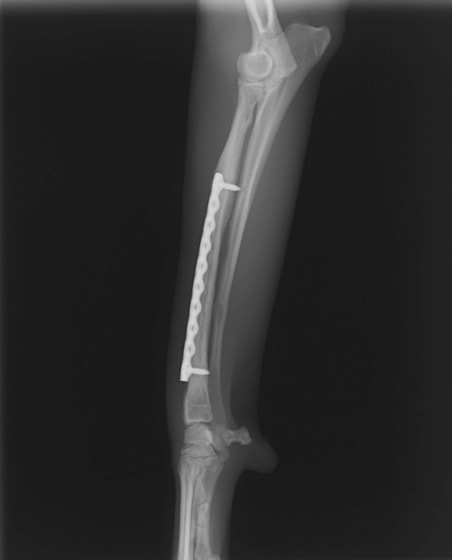

トイプードル 右遠位橈尺骨短斜骨折のALPSによる内固定